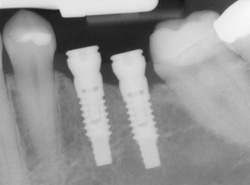

An implant is a synthetic tooth root in the shape of a post that is surgically placed into the jawbone. The “root” is usually made of titanium, the same material used in many replacement hips and knees, and a metal that is well-suited to pairing with human bone. A replacement tooth is then fixed to the post. The tooth can be either permanently attached or removable. Permanent teeth are more stable and feel more like natural teeth.

Dental implants are small screw-shaped titanium posts that function similarly to the root of a natural tooth. Once placed in the jawbone, the posts fuse with the bone to create a solid base for replacement teeth. The presence of the implant stimulates new bone growth in the jaw. However, if a patient has insufficient bone quantity, then a bone graph may be necessary before the implant placement. Most patients undergo implant placement under a local anesthetic. Not all implant dentists provide this service, so patients should inquire beforehand.

When the procedure is complete, we will place a temporary crown or a healing cap over the implant to protect it from food particles and allow the site to heal. A permanent crown or bridge is placed on top of the implant once the healing is complete. Dental implant placement is generally an uncomplicated procedure, although this can vary based on each patient's general and dental health. According to WebMD, dental implants have a success rate of up to 98%. With the right care, implants can last a lifetime and function similarly to natural teeth.